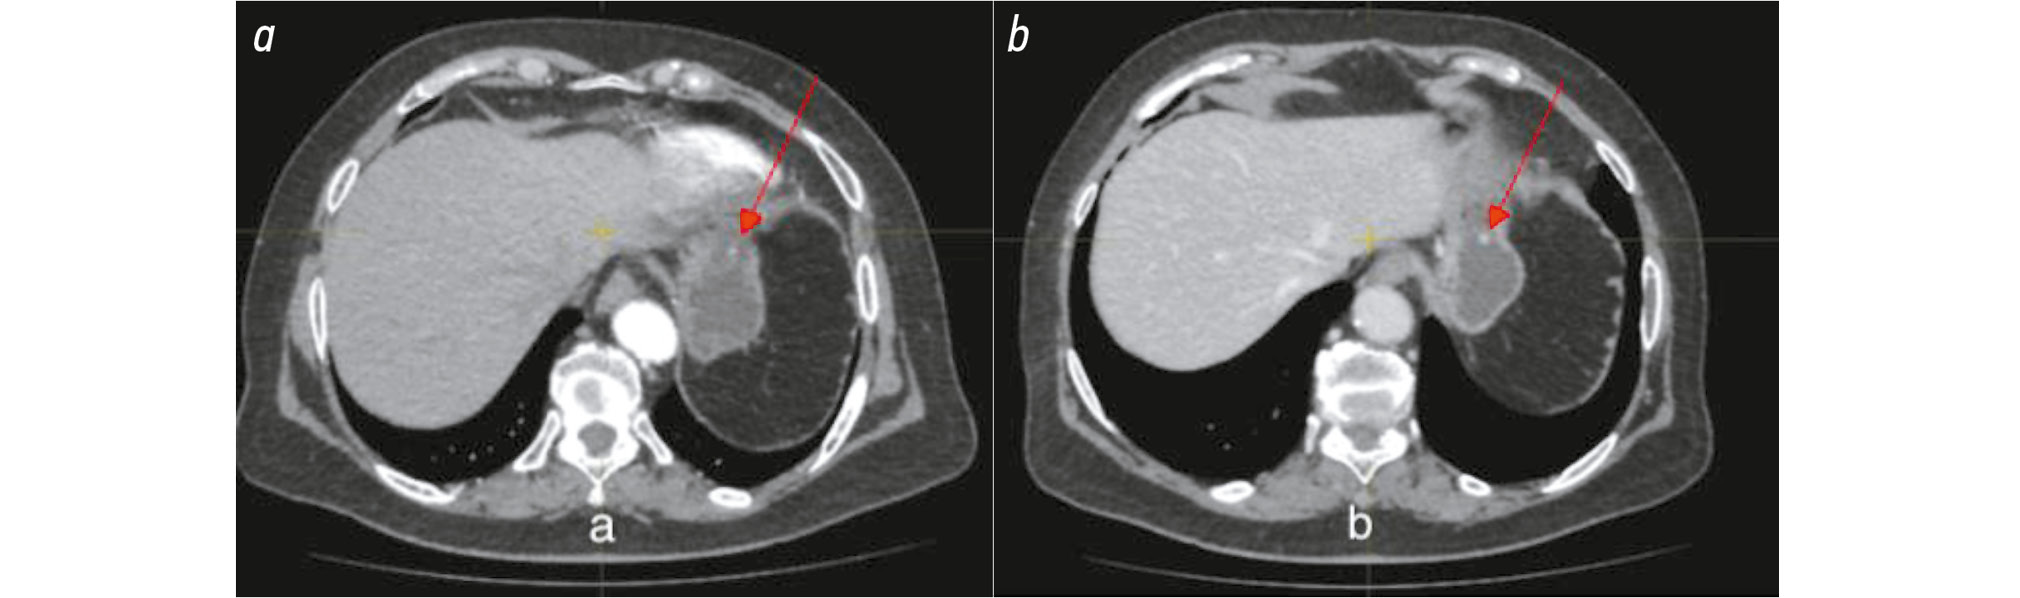

Gastric NETs are generally hypervascular and typically show increased contrast enhancement during the early arterial phase [16]. G1 and G2 gastric NETs are usually small (<1 cm) and are most often located in the gastric fundus or body [10, 17]. Fig. 3 illustrates typical imaging features of gastric NETs. An exophytic, hypervascular lesion measuring 10 × 9 mm is visible along the greater curvature of the gastric body, with strong arterial phase enhancement.

Fig. 3. Gastric neuroendocrine tumor: a, tumor tissue showing high contrast uptake, arterial phase; b, tumor tissue showing moderate contrast uptake, venous phase.